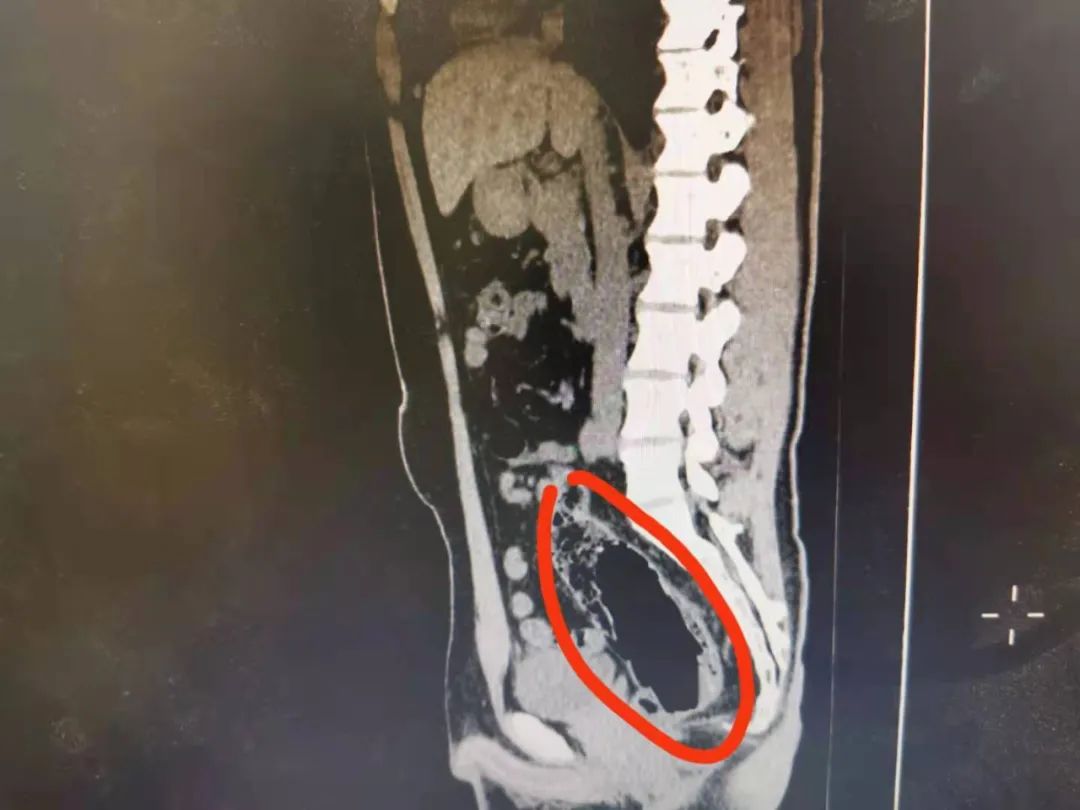

過了一會,病人回來了,告訴老師CT做好了。我也跟着過去瞅了一眼,好傢伙,這東西直徑估計有10cm,長度有20cm,還是個空心的。

又到了大家最喜歡的看圖猜異物環節

請將答案按順序寫在評論區